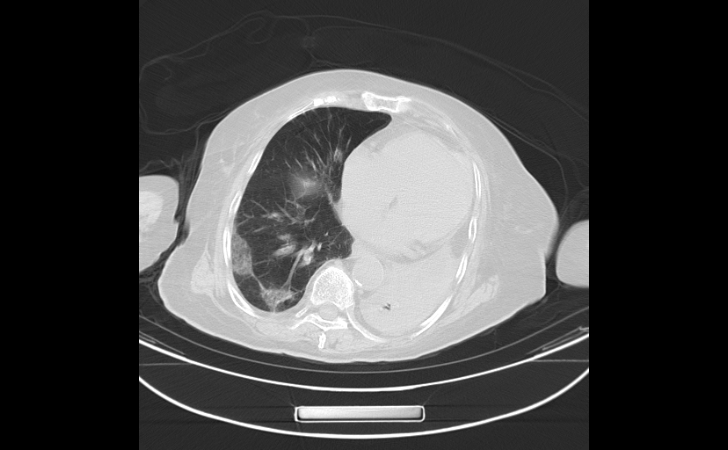

更严重的是,经过胸部CT检查,骆奶奶双肺呈现“白肺”,血氧饱和度降低至85%。这种高龄且有基础疾病的“白肺”老人,死亡率非常高!

经过医护人员的全力治疗和精心护理,骆奶奶病情逐步稳定并好转,胸闷气急症状逐渐消失,血氧饱和度提高到95%,复查胸部CT,“白肺”明显吸收好转。

治疗前/治疗后